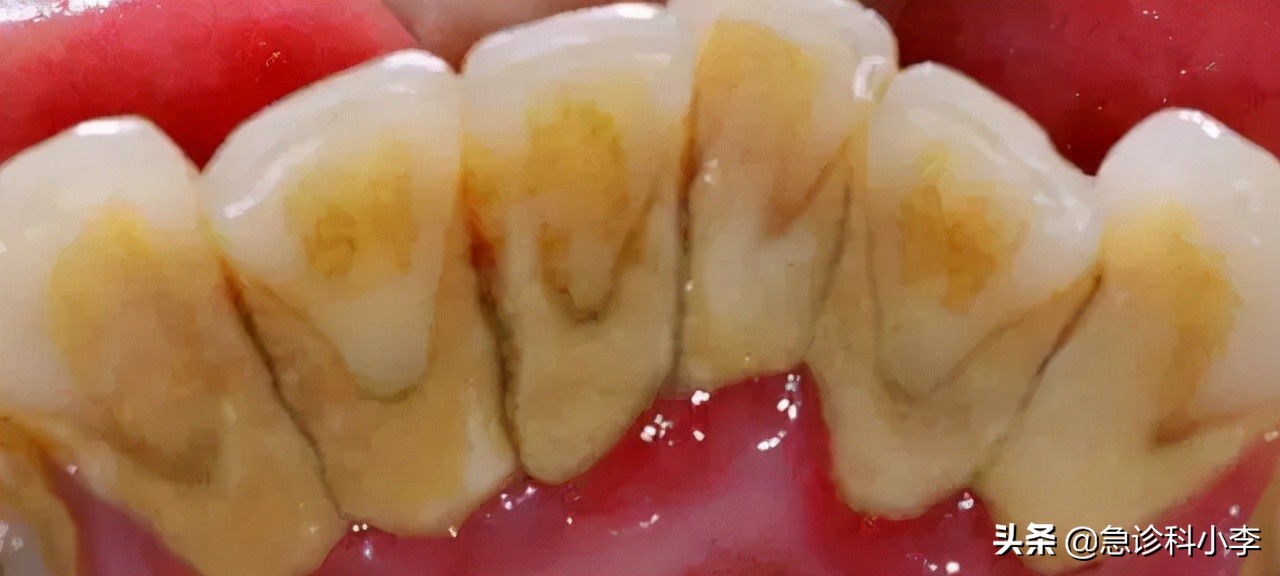

结果显示其 牙结石已到3度 ,并且患有严重的 牙周疾病 ,需要进行口腔治疗,而他认为的碎牙也就是脱落了的牙结石,当在专业仪器中看到布满自己口腔内的那些结石时,赵先生感到一阵反胃。

牙结石通俗来讲就是 牙锈 ,它是存在于 下颚牙齿舌侧面根部、牙齿颈部、上颚后牙颊侧表面以及口腔黏膜无法碰触的牙齿表面 等地方,是一种 唾液中无机盐逐渐沉积在牙齿表面的矿化菌斑及软垢 。

牙结石主要组成成分是磷酸钙、水、有机物、矿酸钙以及钾、钠等微量元素,呈乳白色、黄色、褐色或者是黑色且逐渐硬化,一旦形成极难剔除。

牙结石之于口腔来说算是一种异物,特别是隐秘的龈下结石,其表面粗糙本身极易吸附有害细菌 使口腔充满异味、牙齿变黄,影响个人美观及交际,同时牙结石也是各种牙周疾病的罪魁祸首 。